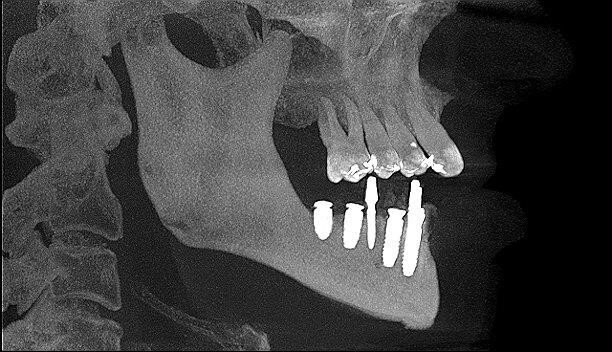

Następnie przytwierdzono ponownie szynę i kolejnymi wiertłami zaopatrzonymi w stopery rozpoczęto preparację łoża dla implantów. Podczas pracy pozyskiwano kość własną pacjenta w celu późniejszej augmentacji. Po przygotowaniu wszystkich miejsc implantacyjnych przystąpiono do wprowadzenia wszystkich 8 implantów poprzez tuleje w szablonie, a następnie usunięto szablon z jamy ustnej pacjenta i założono śruby gojące. Kolejnym etapem pracy było wprowadzenie 5 implantów tymczasowych oraz zaopatrzenie zębodołów poekstrakcyjnych materiałem kostnym własnym pacjenta zmieszanym z materiałem ksenogennym i osoczem. Augmentat pokryto błonami PRF i zaszyto śluzówkę. Wprowadzono antybiotykoterapię. Wykonano zdjęcie CBCT kontrolne po zabiegu.